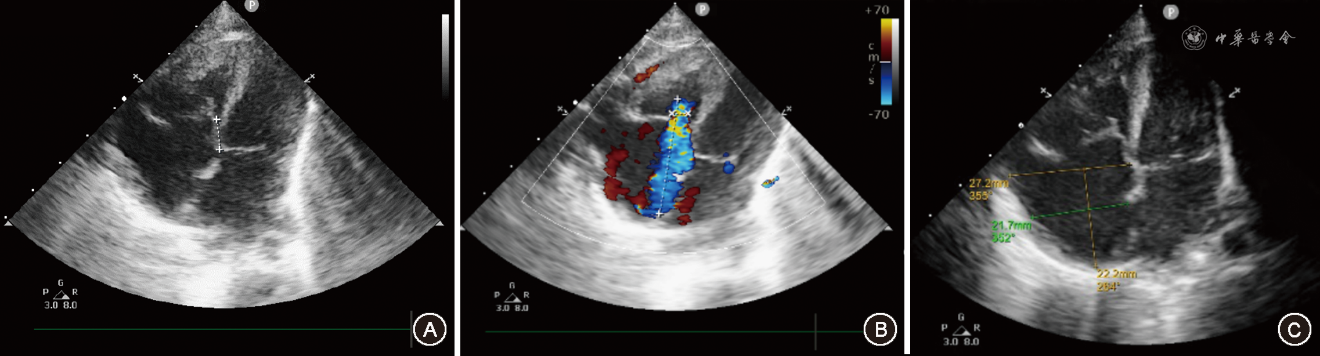

生后2 d心电图检查示:窦性心律,心率120次/min;PR间期缩短,时限75 ms;QRS波群时限108 ms,起始部粗顿形成δ波,V1导联QRS波群呈rS型,Ⅰ、aVL导联δ波呈正向;继发性T波改变,提示B型心室预激(图1)。超声心动图检查示:左、右心房增大,右心房明显,心室大小测值及室壁厚度、活动度均未见明显异常;三尖瓣隔瓣距二尖瓣环间距约7.79 mm,三尖瓣前瓣稍冗长,余各瓣膜形态及活动未见明显异常(图2);降主动脉与左肺动脉间可见分流束,宽约4.8 mm,左向右分流,收缩期分流速度约2.05 m/s,估测肺动脉压约40 mmHg(1 mmHg=0.133 kPa)。提示三尖瓣下移畸形,动脉导管未闭,房间隔卵圆孔未闭,轻度二尖瓣反流,重度三尖瓣反流,轻度肺动脉高压。生后5 d患儿出现心动过速,心电图检查示:无窦性P波,心室率298次/min;窄QRS波,时限60 ms;提示阵发性室上性心动过速(图3)。患儿三尖瓣下移程度较轻,经内科治疗后病情好转,未出现快速性心律失常,出院后定期随访。